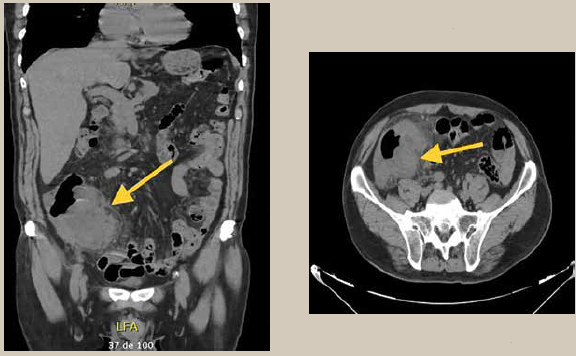

En la tomografía axial computarizada (TAC) abdominopélvica (11-10-2019) en la fosa iliaca derecha se observó una imagen irregular, de bordes definidos de aspecto heterogéneo de predominio hipodenso de 27-34 uh de 77 × 62 × 67 mm, probablemente dependiente de intestino grueso se aprecia estriación de la grasa adyacente.

Conclusión: Imagen en probable relación con mucocele apendicular (figuras 1a y b). Paciente que no presenta datos de irritación peritoneal a nivel abdominal, sin embargo, no se descarta probable necesidad de intervención quirúrgica. Debido a los hallazgos tomográficos se ingresó a piso de Cirugía General para mejorar sus condiciones, iniciar terapia antibiótica y protocolizar evento quirúrgico. Se solicitó valoración preoperatoria al servicio de medicina interna, donde se le dio riesgo quirúrgico Goldman II, ASA II, índice cardiaco LEE I.

Se observa imagen irregular, de bordes definidos de aspecto heterogéneo de predominio hipodenso de 27-34 UH de 77 x 62 x 67 mm en fosa iliaca derecha, se aprecia estriación de la grasa adyacente.

Imagen: Valencia Martínez et al.

Figura 1 TAC simple abdominopelvica en corte coronal y transversal